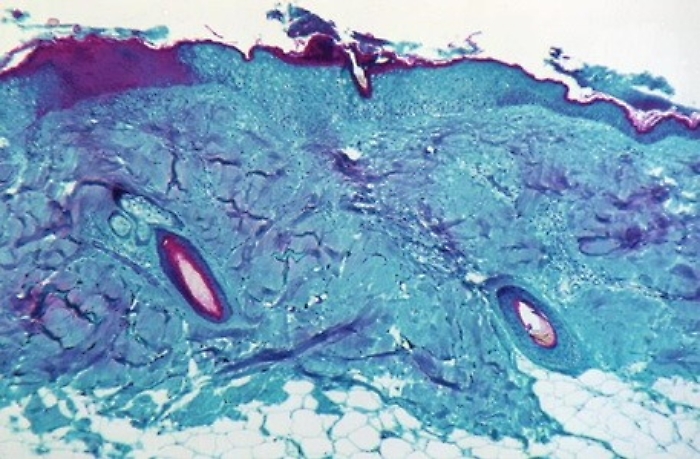

Come per il primo paziente ricoverato, le condizioni cliniche sono sempre state buone. «Gli esperti sottolineano che ci sono diverse patologie di origine infettiva -commenta il Commissario dell’Aou Alessandro Caltagirone - che possono determinare una reazione cutanea simile a quella che abbiamo riscontrato in questi pazienti. È nostro interesse fare il possibile affinché vengano diffuse informazioni corrette e verificate ed è per questa ragione che siamo a disposizione per fornire tutte le notizie utili per verificare le informazioni che possono circolare. In atto non c'è alcun allarme legato al vaiolo della scimmia ed è interesse di tutti noi non alimentare preoccupazione e allarmismi ingiustificati nella popolazione».